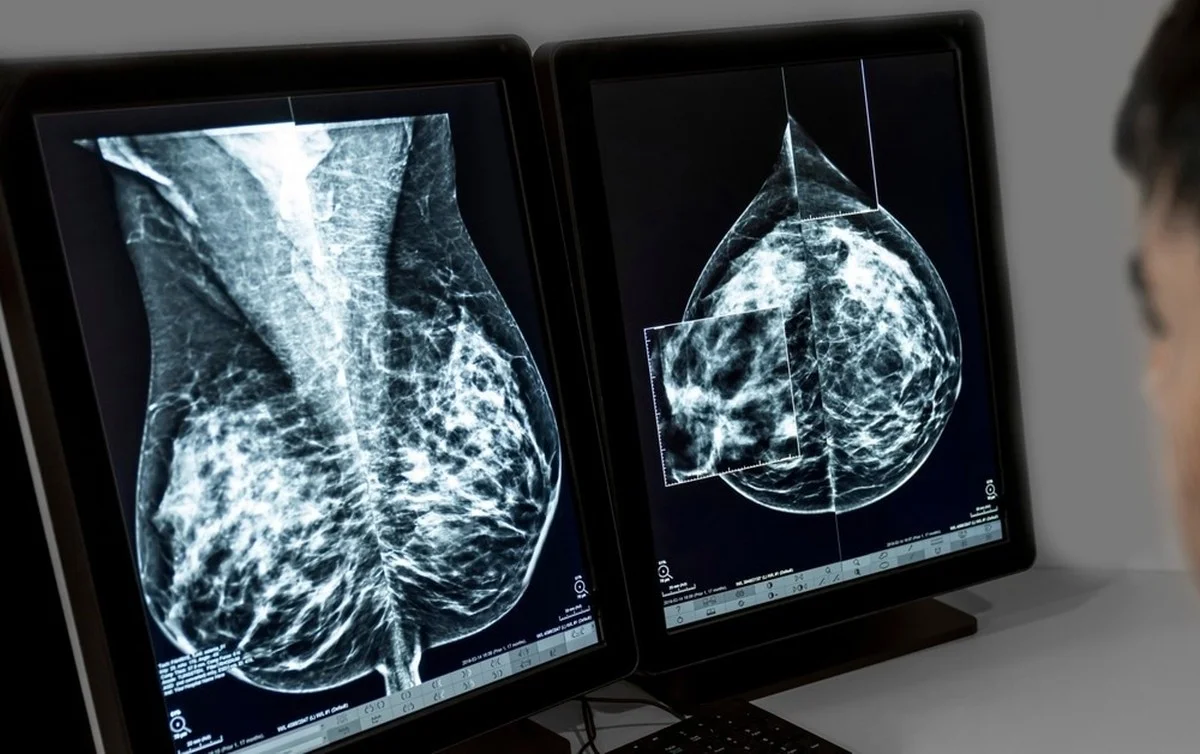

Při mamografii se ukazuje velký problém. Žlázová tkáň je na snímcích bílá. Rakovinotvorné nádory? Ty jsou také bílé. Pokud máte hodně žlázové tkáně (hustá prsa), je to jako hledat sněhovou vločku ve sněhové bouři.

- Zařaďte ultrazvuk (sonografii) do rutiny: Zatímco mamograf dělá rentgenový „výstřel“ (který se potýká s bílými místy), ultrazvuk se dívá na hustotu jiným způsobem. Je to skvělý doplňkový nástroj.